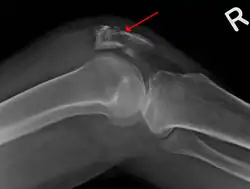

| A fracture of the patella seen on a lateral view | |